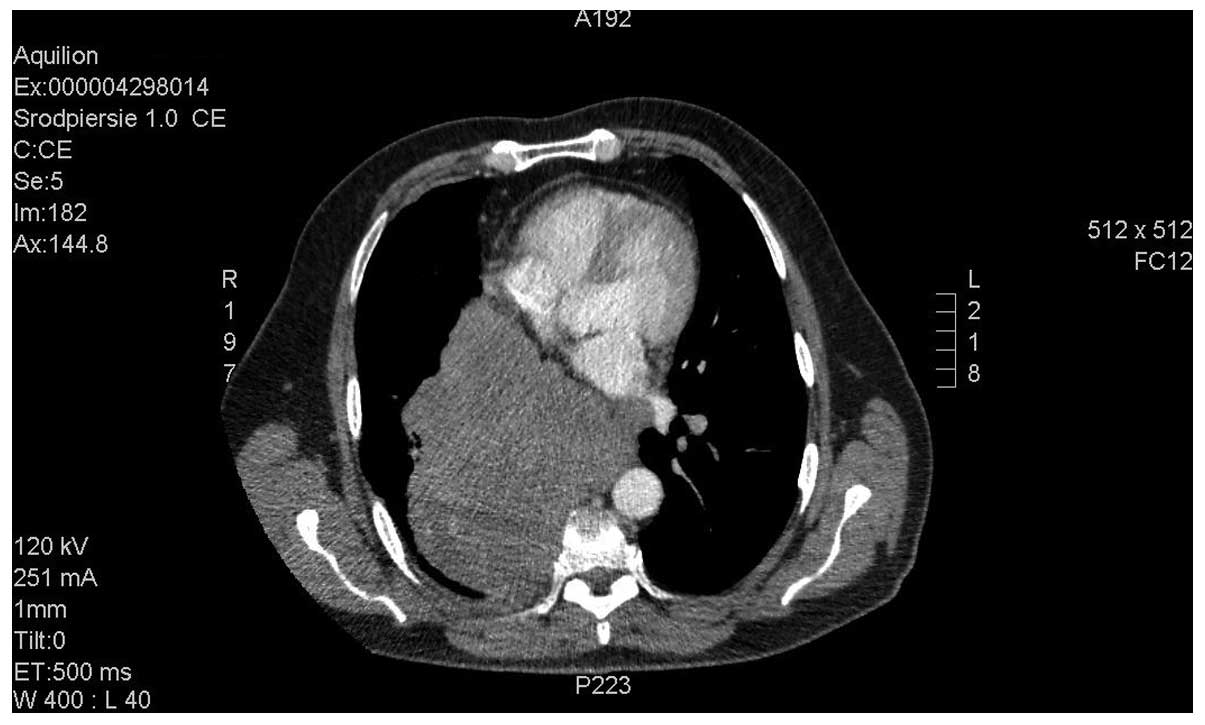

Bradycardia as a rare symptom of cisplatin cardiotoxicity: A case report

Cisplatin (DDP) is one of the most frequently used chemotherapeutic agents, and has a characteristic toxicity profile. For DDP, complications affecting the cardiovascular system, which are typical for certain other agents, are rare; however, their occurrence may lead to life‑threatening conditions. To the best of our knowledge, there are few reported cases of DDP‑induced bradycardia in the relevant medical literature. The current report presents the case of a 58-year-old patient diagnosed with metastatic neuroendocrine carcinoma with a primary lesion in the posterior mediastinum, who was treated with DDP and etoposide chemotherapy. Following the initial chemotherapy cycle, the patient experienced severe symptomatic bradycardia (a drop in heart rate to 40 bpm), with the corrected QT interval prolonged to 424 msec. The patient's condition required close monitoring and treatment. Similar symptoms occurred following each of the three cycles of chemotherapy. Imaging studies performed following the third treatment cycle revealed disease progression, and the patient was referred for palliative care. Reports have indicated that damage to the cardiovascular system, including cardiac ischemia, diastolic disturbances, hypertension and microalbuminuria, may be associated with DDP‑based therapy. However, the mechanism of DDP‑associated cardiac toxicity remains to be elucidated. It may be induced by factors including direct toxicity, ion imbalance, heart infiltration and, in the case of neuroendocrine tumors, the influence of tumor excretions.

Figure 1

Figure 2